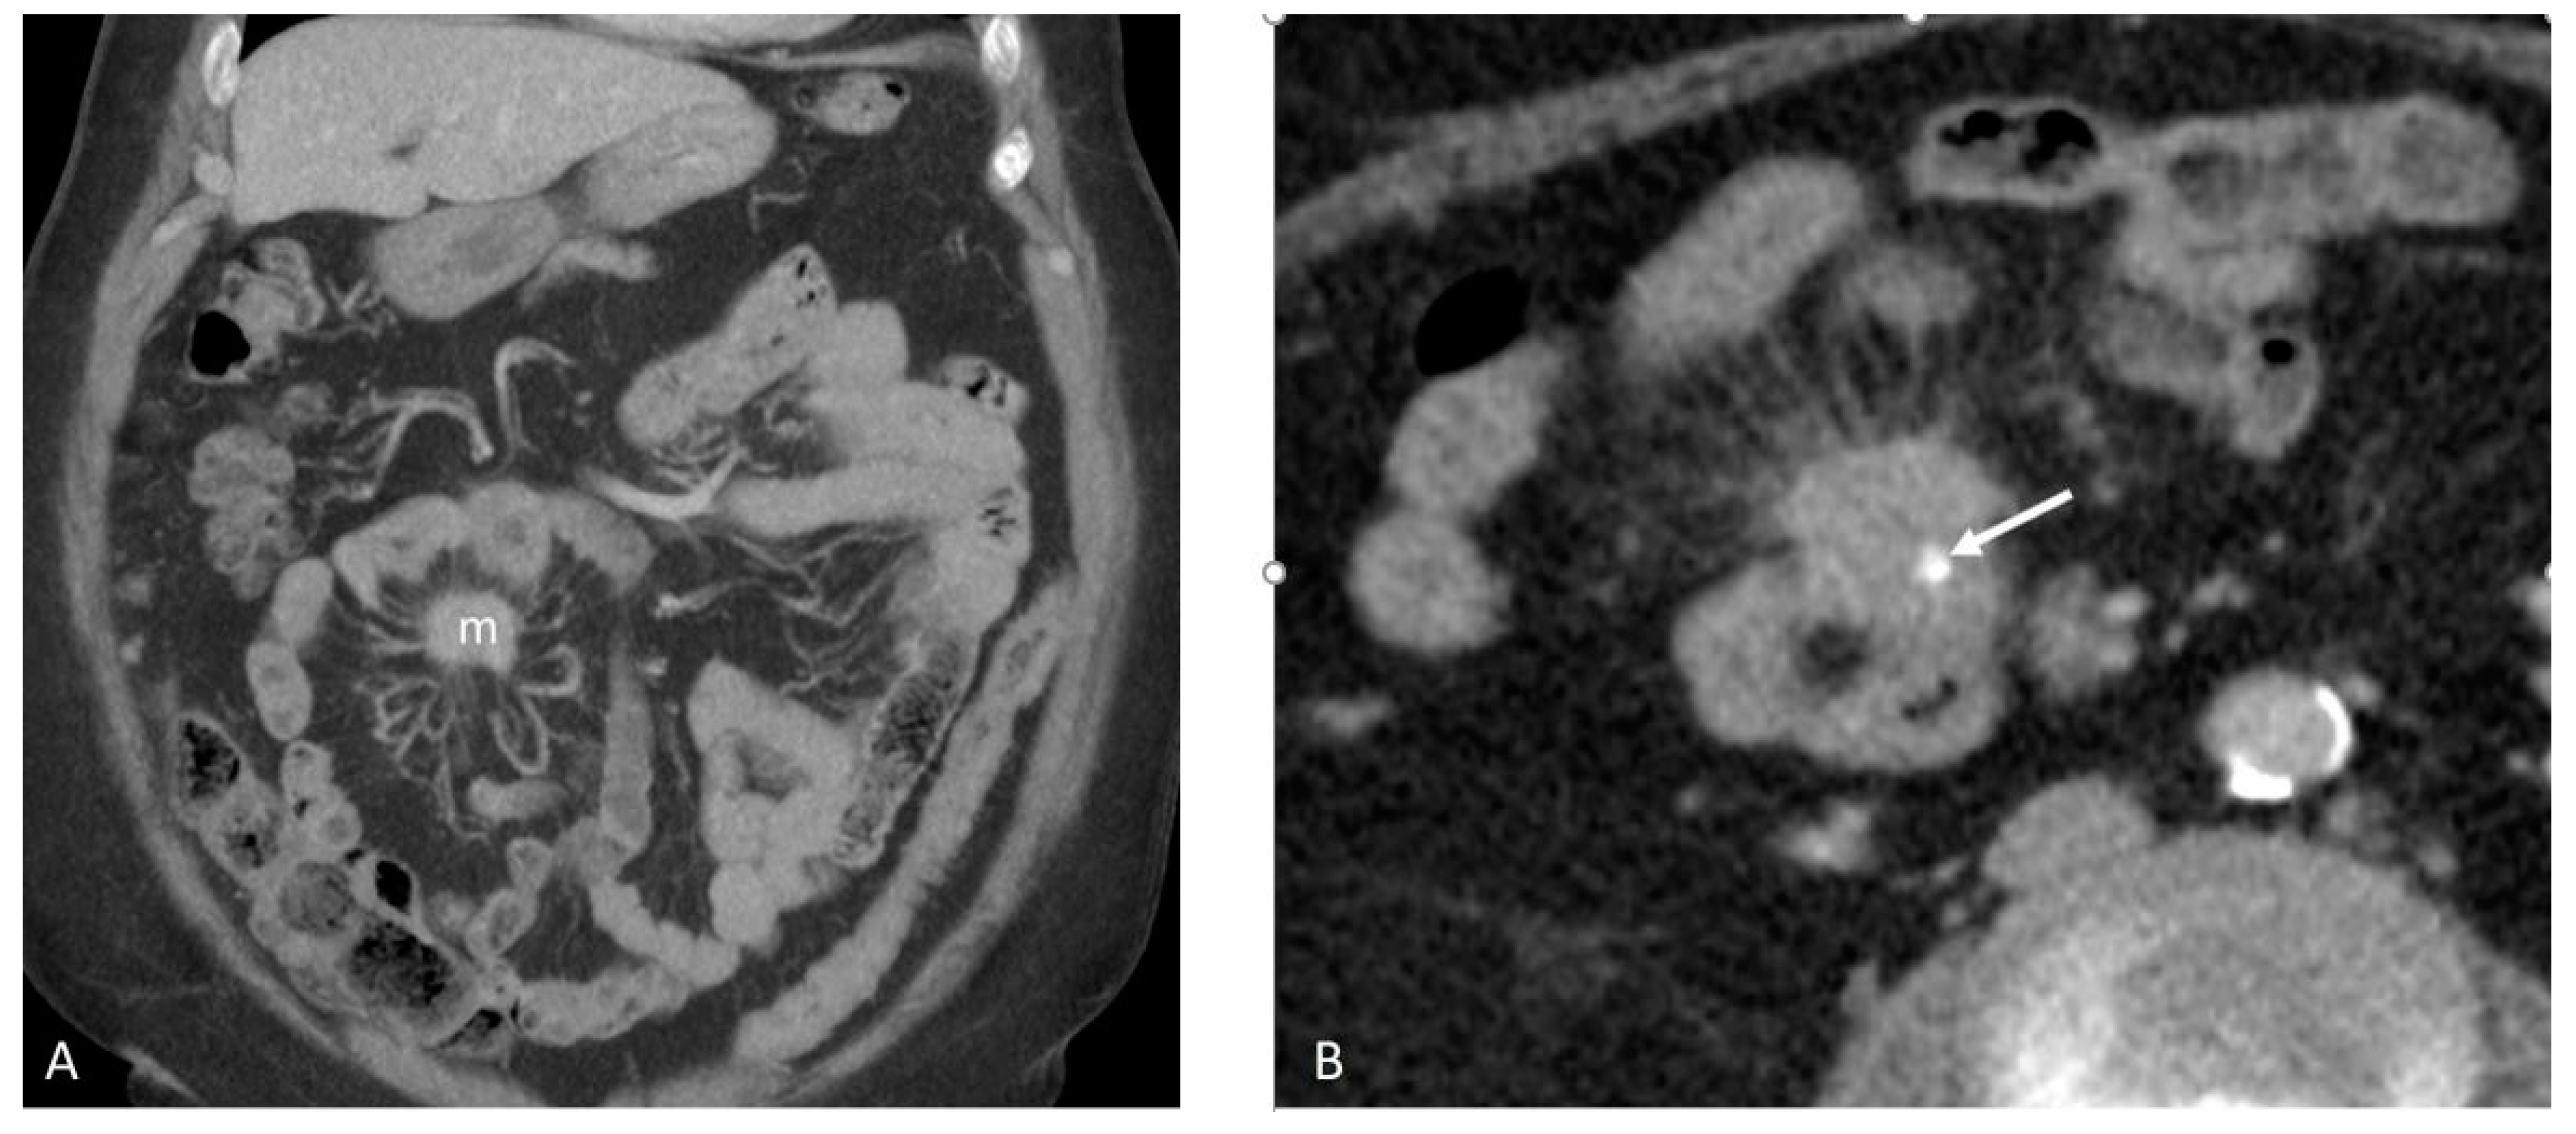

3.2. Mesenteric Fibrogenesis and Extramural Vascular Invasion